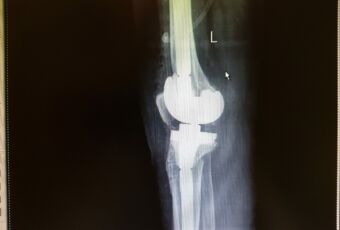

- Наименование операции: ревизионное эндопротезирование коленного сустава.

- Используемое оборудование, методика: использовался специальный установочный инструментарий для имплантации полусвязанного эндопротеза коленного сустава LCCK Zimmer, методика операции: удаление нестабильного компонента тотального эндопротеза коленного сустава, подготовка поверхностей костной ткани к имплантации ревизионного компонента, примерка компонентов эндопротеза, установка ревизионных связанных компонентов при помощи костного цемента. Операция – ревизионное эндопротезирование коленного сустава связанным эндопротезом.

- Краткая информация о пациенте, диагноз: Пациентка С., 1952 г.р. Диагноз: Асептическая нестабильность компонентов эндопротеза левого коленного сустава.

- Краткое описание хода операции (основные этапы): Иссечены рубцовые ткани по периферии сустава. Удален полиэтиленовый вкладыш и два винта с шайбами из бугристости большеберцовой кости. Затем с помощью долот и набойников удалены последовательно бедренный и большеберцовый компоненты. По направителям произведены минимальные опилы большеберцовой и бедренной костей. Затем развертками обработан канал большеберцовой кости до размера 14 мм, а бедренной кости до 17 мм. Имплантированы примерочные компоненты на интрамедуллярных ножках, отмечены дефекты, требующие заполнения металлическими блочками и стабильность сустава. После этого на 1 дозу костного цемента имплантированы бедренный компонент («Е») LCCK с ножкой 100/17 мм, большеберцовое плато 4 с ножкой оффсетной 100/14 мм, вкладыш LCCK 14 мм, 3 металлических блочка. Сустав вправлен, стабилен.

- Результат: имплантация ревизионного эндопротеза коленного сустава.